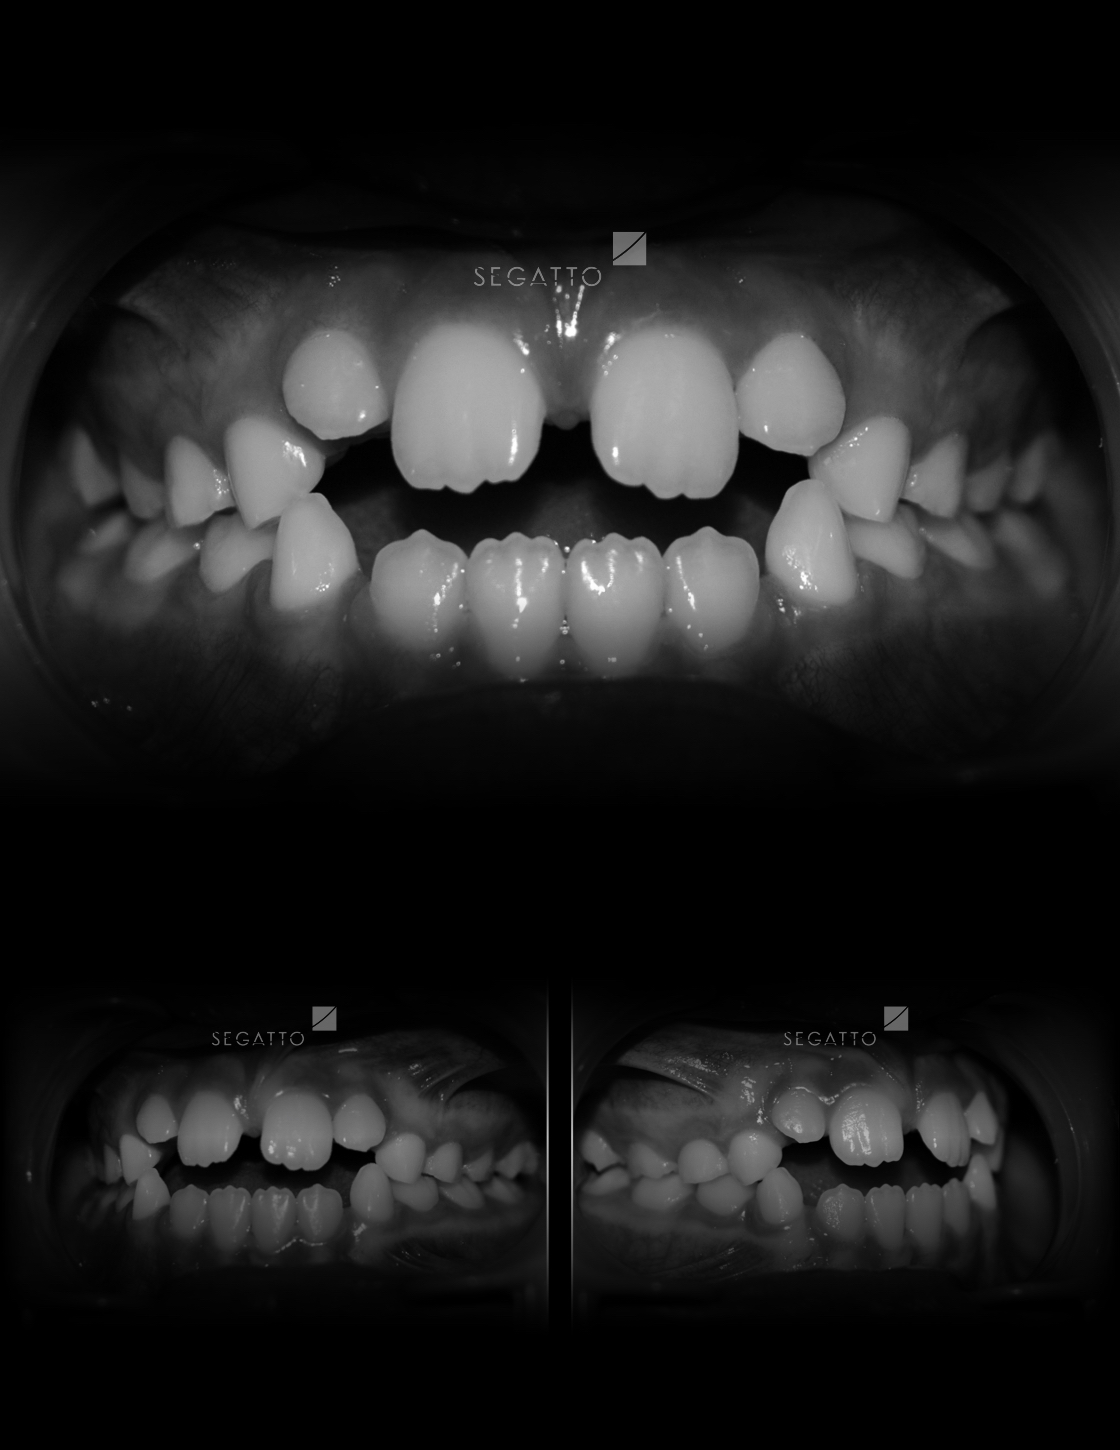

Orthodontics

Cases